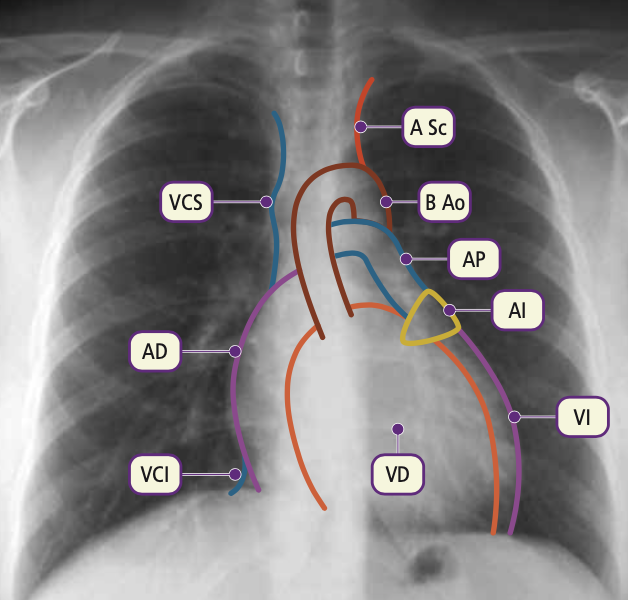

Observa y nombra la silueta de las diferentes estructuras que forman el mediastino.

El borde derecho está formado de arriba hacia abajo por el tronco braquiocefálico derecho, la vena cava superior (VCS), la aurícula derecha (AD) y una pequeña parte de la vena cava inferior (VCI).

En el lado izquierdo la parte superior representa la silueta de la arteria subclavia (A Sc) que se continúa con la prominencia del botón aórtico (B Ao).

En la parte media se proyecta el tronco de la arteria pulmonar (AP); parte de la aurícula izquierda (AI) y el ventrículo izquierdo (VI), que forma un arco fuertemente prominente y delimita el ápex cardiaco.

VCS: Vena cava superior. AD: aurícula derecha. VCI: Vena cava inferior. A Sc: Arteria subclavia. B Ao: Botón aórtico. AP: Arteria pulmonar. AI: Aurícula izquierda. VI: Ventrículo izquierdo. VD: ventrículo derecho.